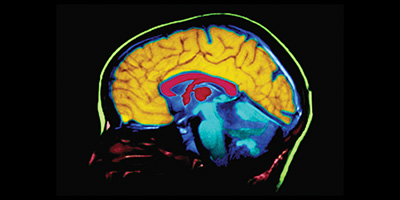

El Alzheimer y el cerebro

Los cambios microscópicos en el cerebro comienzan mucho antes de que aparezcan las primera señales de pérdida de memoria. El cerebro tiene 100 mil millones de células nerviosas (neuronas). Cada célula nerviosa se conecta con muchas otras para formar redes de comunicación. Los grupos de células nerviosas tienen tareas especiales. Algunos ayudan a pensar, aprender y recordar. Otros ayudan a ver, escuchar y oler.

Para hacer su trabajo, las células del cerebro funcionan como pequeñas fábricas. Reciben suministros, generan energía, construyen equipos y se deshacen de los desperdicios. Las células también procesan y almacenan información y se comunican con otras células. Mantener todo el sistema en funcionamiento requiere coordinación y grandes cantidades de combustible y oxígeno. Los científicos creen que la enfermedad de Alzheimer impide que partes de las fábricas de las células funcionen correctamente. No están seguros de dónde comienza el problema. Pero igual que sucede en una fábrica real, las averías y los atascos en un sistema causan problemas en otras áreas. A medida que el daño se extiende, las células pierden su capacidad de trabajar y, finalmente, mueren. Esto causa cambios irreversibles en el cerebro.

Realice nuestro, Paseo interactivo por el cerebro para ver cómo el Alzheimer afecta la salud del cerebro.